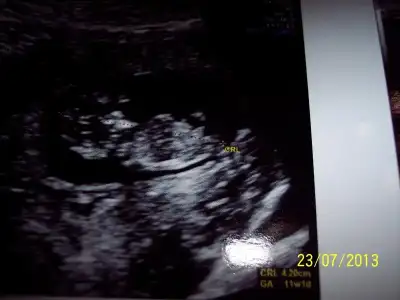

kızlar ilk defa resim yüklüyorum.11+4 üz.yorumlayan arkadaşlara şimdiden teşekkkürler.ORKDM neredeysen sen de bir bak.meraktan mahvoldum.

orkişimmmm nasıl hayal ederdim bi gün ben de arkadaşımın topiğine resim koyacam diyeee...hep bu anı hayal ederdim.....tatilden dönmene daha çokkkkkk var ama olsunnnnnn ben yine de koyacammmmm....10+2 ve 11+2 burda....pek belli de değil ama:1::1::1::1::1::1: olsunnnn :52::52::52::52::52::52::52::52:[ $001.webp $002.webp $043.webp $045.webp $046.webp